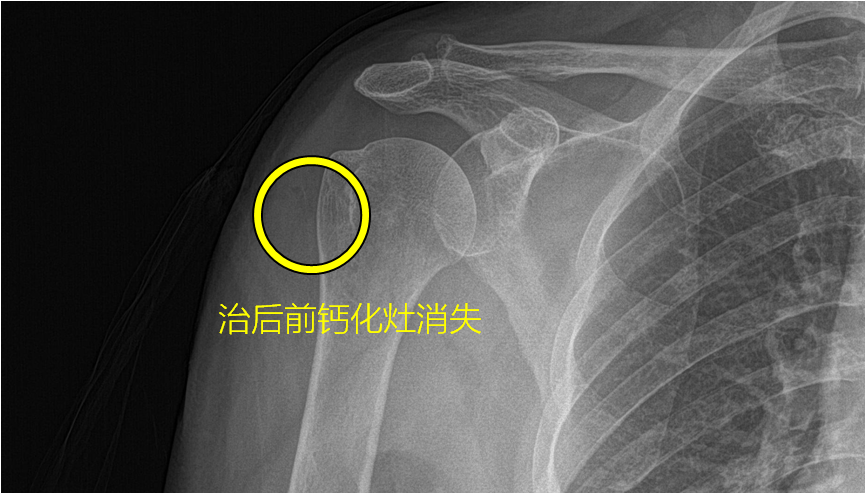

王阿姨最近遇到了遇到了一个烦心事,一个多月前的某一天,王阿姨突然觉得自己右肩关节疼痛剧烈,痛的生活没法自理,动也不能动,痛的睡不着,就像肩关节被咬住的撕扯痛,还会“一跳一跳”的痛,到医院就诊发现,肩关节接近腋下的位置长了一个“钙化灶”,医生告诉王阿姨,这个叫肩袖钙化性肌腱炎,而且病灶的位置在肱骨近端外侧,先用药物治疗包括非甾体类抗炎止痛药、再用冲击波物理治疗,如果实在不行可以超声导引下找到病灶穿刺看看能不能讲这个病灶内的钙化物质抽出来。 那为什么会发生钙化性肌腱炎呢? 大部分钙化性肌腱炎原因不是特别明确,可能与外伤、慢性炎症等有一定相关性,会在病变部位出现大量羟基磷灰石沉积,诱发炎症,产生强烈刺激,出现非常剧烈的疼痛,如同古代文献中对“白虎历节”所描述的“痛如虎咬”,对患者的生活质量产生非常严重的影响。 诊断上除了患者的症状,在X线片上可看见高密度病灶影作为诊断依据。CT、磁共振可以精准的定位病灶,具有较高水平的超声检测也可以帮助诊断、定位钙化灶。 治疗上,首选药物治疗即非甾体类抗炎药,同时冰敷也能起到镇痛效果,如果效果不明显可以逐步采用局部糖皮质激素治疗、体外冲击波、超声导引钙化灶穿刺抽吸术等治疗,如果各类保守治疗效果均不理想,可采用肩关节镜手术治疗也具有创伤小、效果好、恢复快等优点。 王阿姨在这一个月里尝试了各种治疗方案,包括但不限于非甾体类抗炎药口服、体外冲击波治疗、局部封闭治疗,局部封闭治疗起了几天效果,后又不舒服了,整晚整晚睡不着觉,还在超声导引下穿刺病灶,但是均没有取得较好效果,最后在关节科住院进一步查了CT、MR定位后,行了关节镜下清理并修补了破损的肩袖,术后3天出院,痛了一个多月的王阿姨终于感受到了久违的舒畅。 作者:上海中医药大学附属岳阳中西医结合医院 骨伤中心关节外科 冯圣一,李学家,李勃 上海市虹口区曲阳路街道社区卫生服务中心 针伤科 陆文婷 延伸阅读